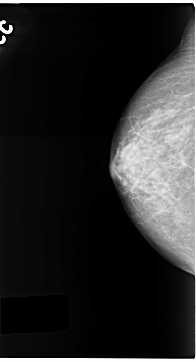

C_0141_1.RIGHT_CC

RIGHT_CC LINES 4704 PIXELS_PER_LINE 2544 BITS_PER_PIXEL 12 RESOLUTION 50 NON_OVERLAY